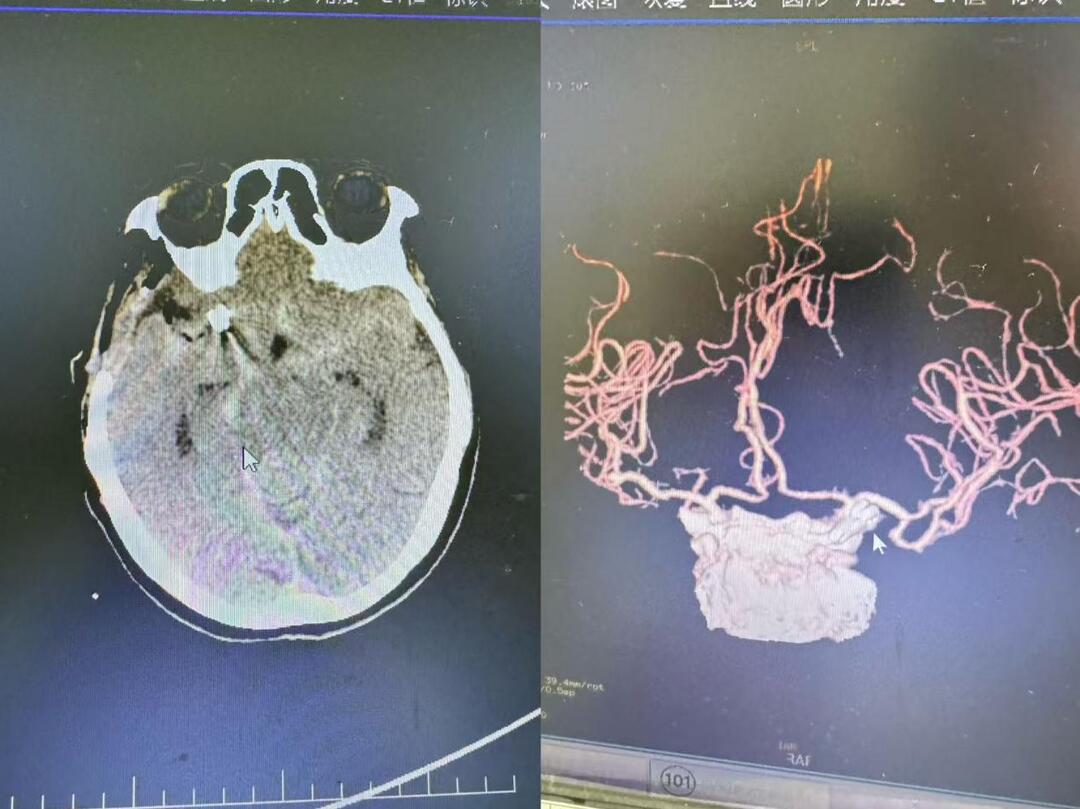

经急诊入院后,医疗团队立即为患者启动卒中绿色通道,完成头部CT平扫检查,影像学结果显示广泛蛛网膜下腔出血。神经外科副主任医师刘银川紧急会诊后,结合患者突发剧烈头痛、颈项强直等典型临床表现,初步判断为颅内动脉瘤破裂所致。为明确责任血管,医院多学科协作快速实施颅脑CT血管造影(CTA)检查,最终确诊为右侧颈内动脉交通段囊状动脉瘤(直径约5.2mm),该病变位置特殊,毗邻重要神经血管结构,属于神经外科急危重症。

术后复查影像